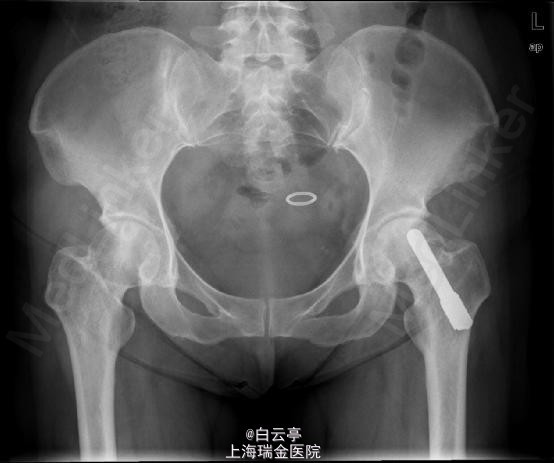

诊断:双侧股骨头坏死。 治疗:左侧:钻孔减压+对侧髂骨移植+钽棒植入。右侧: 钻孔减压

随访:3月后部分负重。半年后完全负重。3年后股骨头坏死未进展。 讨论: 对于股骨头坏死患者,软骨塌陷之前,行钽棒植入术能延缓THA术的时间。因此,对于年轻患者,股骨头尚未塌陷的患者,可先行钽棒植入手术。对于坏死病灶很小的患者,可单纯行钻孔减压。